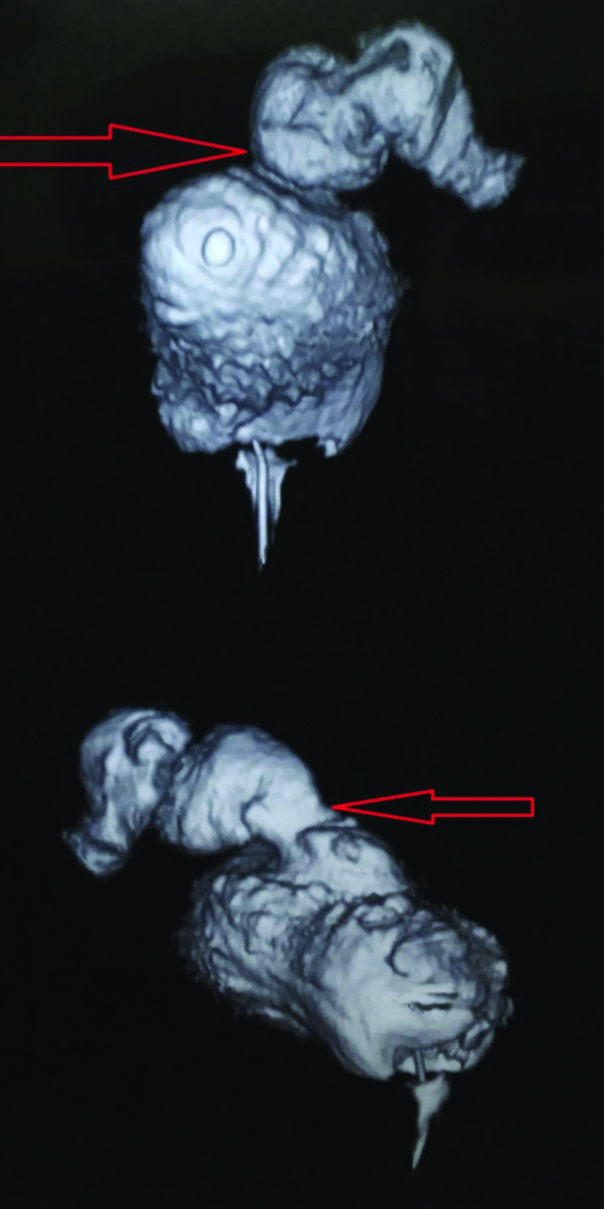

3D CT showing enterovesical fistula.

Patient was referred to us, on his second postoperative day. On examination, abdomen was soft, non distended and non tender, vitals were stable. Drain fluid creatinine was measured and found to be 56 mg/dL. Simultaneous serum creatinine was 1.5 mg/dL. Contrast “enhanced” CT scan was done which revealed intraperitoneal bladder perforation, pneumoperitoneum and a cysto-enteric fistula with contrast going into the small intestine [Table/Fig-1,2,3 and 4]. Though, it was an intraperitoneal bladder rupture with a cysto-enteric fistula a conservative management was planned, as there were no abdominal signs with stable vitals. In further course, patient developed a left lumbar lump containing purulent material, which was drained subsequently.